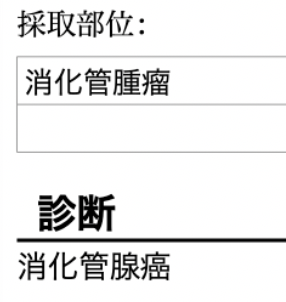

⬇️手術後1週間ほどして病理検査結果が出ました。

病理(細胞の検査)結果は『消化管腺癌』、悪性腫瘍でした。

手術で完全切除していても、お腹の中やリンパ節に転移、再発する可能性が高い腫瘍でした。